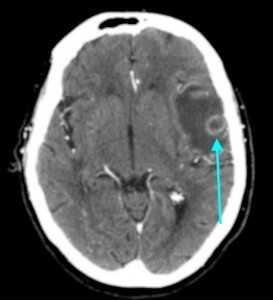

МРТ-признаки метастазов в мозг

МРТ — более чувствительный и специфичный метод в выявлении метастазов ЦНС по сравнению с компьютерной томографией. Вторичные опухоли имеют ряд общих черт при МР-исследовании.

Т1 ВИ (без контрастного усиления)

- Изоинтенсивный либо умеренно гипоинтенсивный сигнал по отношению к белому веществу мозга от активной части опухоли

- Гипоинтенсивный сигнал от центральной зоны (некроза и распада)

Т2 ВИ

- Гиперинтенсивный сигнал от центрального участка метастаза

- Повышение интенсивности сигнала от отечных тканей мозга, окружающих вторичную опухоль, вследствие чего метастазы становятся более четкими на изображениях

МРТ с контрастным усилением

- Выраженное увеличение интенсивности сигнала

- Усиление сигнала по периферии в виде «кольца» или «короны»

- Помогает дифференцировать кровоизлияиния в метастаз от геморрагического инсульта (выраженное усиление сигнала на Т1 ВИ)

Метастазы головного мозга на МРТ. Фото. Определяются множественные метастазы в мозг при раке легкого: слева в режиме Т1-ВИ в виде гипоинтенсивных образований, справа — в режиме Т2-ВИ виде множественных участков повышенного сигнала, окруженных зоной перифокального отека. У пациента подтверждена первичная опухоль легкого.